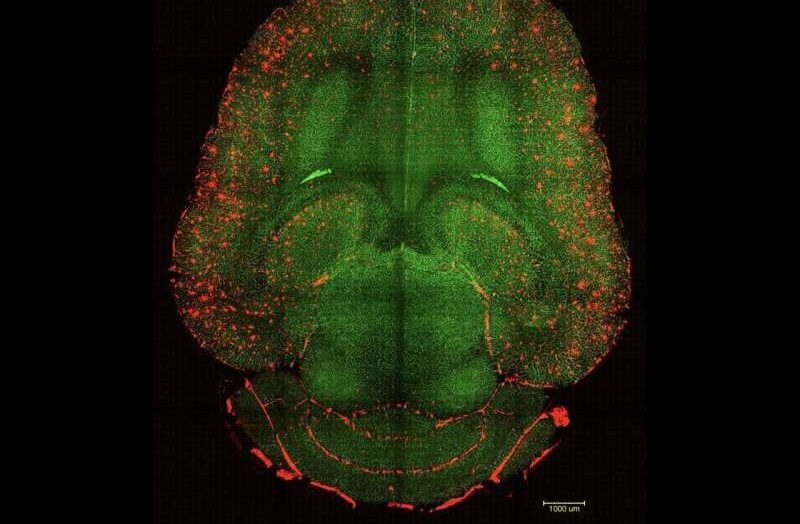

Miçiqan Universiteti tərəfindən Robert Egan tərəfindən redaktə edilmişdir Redaktorların qeydləriKredit: Pixabay/CC0 Public Domain Miçiqan Universitetinin Kresge Eşitmə Tədqiqat İnstitutu və Roçester Universitetinin rəhbərliyi ilə aparılan tədqiqatlar insanların səs-küylü mühitlərdə tək səsləri seçə və onlara fokuslana biləcəyi mexanizmləri işıqlandırır. https://googleads.g.doubleclick.net/pagead/ads?gdpr=0&us_privacy=1—&gpp_sid=-1&client=ca-pub-0536483524803400&output=html&h=280&slotname=7587637799&adk=1434173251&adf=4198688998&pi=t.ma~as.7587637799&w=750&fwrn=4&fwrnh=0&lmt=1759824906&rafmt=1&armr=3&format=750×280&url=https%3A%2F%2Fmedicalxpress.com%2Fnews%2F2025-10-human-ability-focus-specific-auditory.html&fwr=0&rpe=1&resp_fmts=3&wgl=1&aieuf=1&uach=WyJXaW5kb3dzIiwiMTkuMC4wIiwieDg2IiwiIiwiMTQwLjAuNzMzOS4xMjgiLG51bGwsMCxudWxsLCI2NCIsW1siQ2hyb21pdW0iLCIxNDAuMC43MzM5LjEyOCJdLFsiTm90PUE_QnJhbmQiLCIyNC4wLjAuMCJdLFsiR29vZ2xlIENocm9tZSIsIjE0MC4wLjczMzkuMTI4Il1dLDBd&abgtt=6&dt=1759824906402&bpp=2&bdt=321&idt=33&shv=r20251006&mjsv=m202510020101&ptt=9&saldr=aa&abxe=1&cookie=ID%3De77740426f8da9bc%3AT%3D1735295852%3ART%3D1759824811%3AS%3DALNI_MbHbvhLj3WydQ3lYshQhNgDg8E9nQ&gpic=UID%3D00000f80ad9e2337%3AT%3D1735295852%3ART%3D1759824811%3AS%3DALNI_MYM9zSDwUrvOLsQ-H1E20L0IjGeMw&eo_id_str=ID%3Df152d1a4517561f1%3AT%3D1751526315%3ART%3D1759824811%3AS%3DAA-AfjYXsAMYxawkCSjU_EMOR4gg&prev_fmts=0x0&nras=1&correlator=2581614963566&frm=20&pv=1&rplot=4&u_tz=240&u_his=1&u_h=1080&u_w=1920&u_ah=1032&u_aw=1920&u_cd=24&u_sd=1&dmc=8&adx=448&ady=1115&biw=1905&bih=945&scr_x=0&scr_y=0&eid=31095048%2C31095050%2C31095053%2C31095055%2C31095080%2C95370627%2C95372358%2C95344790&oid=2&pvsid=5582994390982312&tmod=2120451577&uas=0&nvt=1&ref=https%3A%2F%2Fphys.org%2F&fc=1920&brdim=0%2C0%2C0%2C0%2C1920%2C0%2C1920%2C1032%2C1920%2C945&vis=1&rsz=%7C%7CpeEbr%7C&abl=CS&pfx=0&fu=128&bc=31&bz=1&td=1&tdf=2&psd=W251bGwsbnVsbCxudWxsLDNd&nt=1&ifi=2&uci=a!2&btvi=1&fsb=1&dtd=175 Əvvəlki tədqiqatlar müəyyən etmişdi ki, “ seçimli diqqət ” adlanan səsi süzmək qabiliyyəti beynin eşitmə qabığını əhatə edir. Bununla belə, bu seçici […]